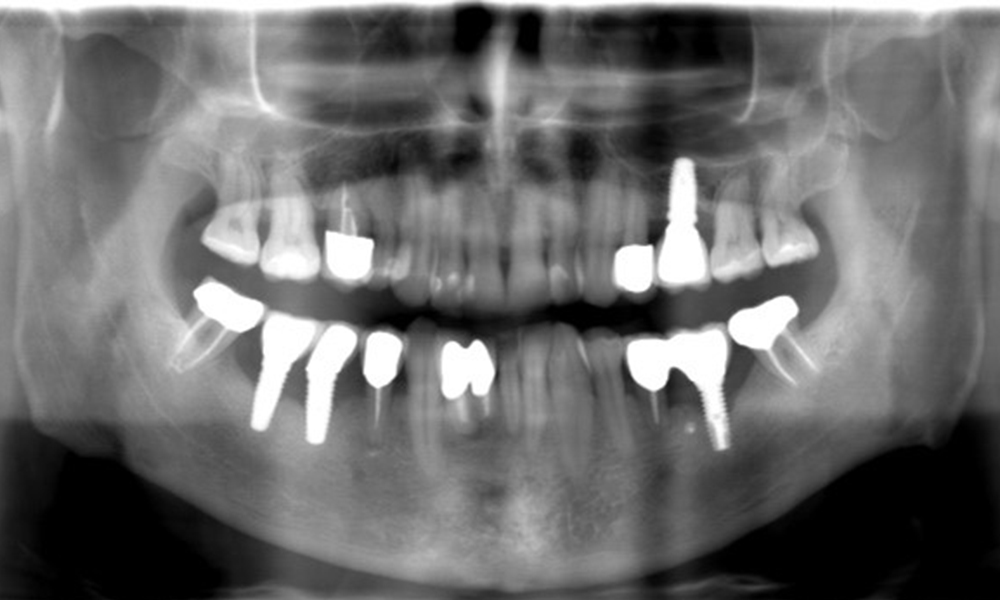

Ein 52-jähriger Patient stellt sich zur Präventionssitzung vor. Der Patient hat keine Allgemeinerkrankungen und nimmt keine Medikamente ein. Er hat verschiedene zahnärztliche Versorgungen und zudem zwei aktive kariöse Läsionen. Außerdem verfügt der Patient über vier Implantate (2., 3. und 4. Quadrant). Es zeigt sich eine parodontale Vorerkrankung (Stadium IV, Grad B). Derzeit herrschen stabile parodontale Verhältnisse, lediglich am Implantat regio 36 zeigen sich Sondierungstiefen (ST) von 5 mm. Zudem lässt sich eine Gingivitis feststellen.

Der Patient zeigt keine besonderen anamnestischen Risikofaktoren mit spezifischen zahnmedizinischen Auswirkungen. Daher ist der aus der Mundgesundheit ermittelte Bedarf maßgebend. Hierbei zeigt sich am Implantat im 3. Quadranten ST von 5 mm und im Röntgenbild eine Zunahme des Knochenverlustes. Der Patient hat zudem eine aktuell stabile parodontale Vorerkrankung und zwei aktive initialkariöse Läsionen.

Röntgenaufnahme zeigt Verlauf des Knochenabbaus

"Die Röntgenaufnahmen zeigen den Verlauf des Knochenabbaus. OPG vom 29.06.2020 (links) und OPG vom 26.02.2024 (rechts)